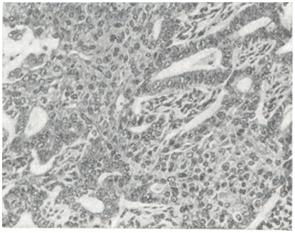

В большинстве случаев аденоакантома относят к аденокарциномам различных органов с явлениями плоскоклеточной метаплазии (повидимому, ложной) железистого эпителия (смотри Рак), иногда с образованием роговых масс, вплоть до формирования раковых «жемчужин». Аденоакантома встречается в пищеводе, обычно в зоне пищеводно-желу-дочного перехода, в желудке, желчном пузыре, поджелудочной железе, прямой кишке, анальном канале, влагалище, матке, яичниках (рис. 1.), коже, потовых железах. Макроскопически аденоакантома практически не отличима от картины железистого рака соответствующего органа. Микроскопически в опухоли наряду со структурой аденокарциномы обычно обнаруживают ряд фаз гетероплазии железистого эпителия в многослойный плоский. Оба структурных компонента аденоакантомы с различными признаками дифференцировки эпителия бывают, расположены в одних и тех же участках и интимно связаны между собой.